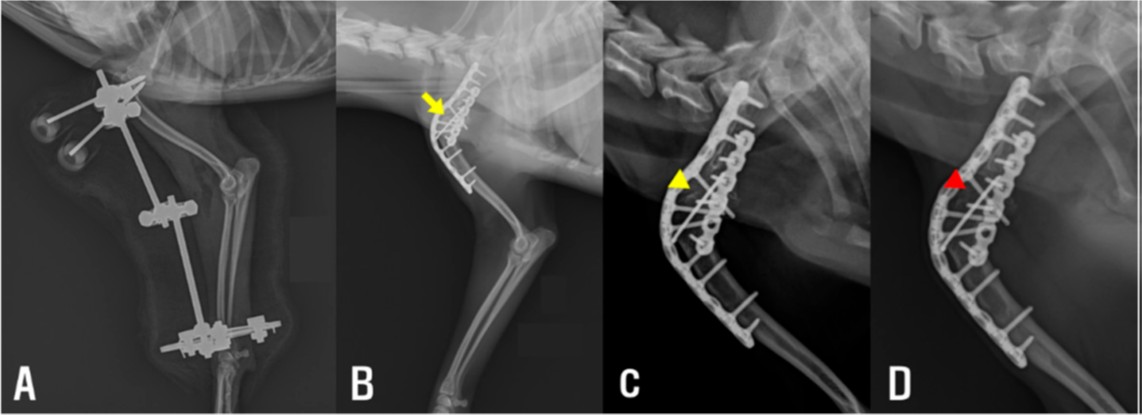

图3. (A) 肘部肌肉松解术后即刻,肘伸展及关节对位明显改善。(B) 肩关节融合术后即刻,内植物位置合适,融合处可见间隙(黄色箭头)。(C) 肩关节融合术后1个月,融合处间隙较术后即刻缩小(黄色箭头)。(D) 肩关节融合术后4个月,融合处间隙几乎完全消失(红色箭头)。

随后数周肘伸展逐渐改善,非负重跛行发作频率减少。肩关节融合术前复测ROM:右肘屈20°/伸148°,左肘屈22°/伸142°,肘功能基本恢复。

术后1周出院,嘱居家限制活动,继续肘腕被动ROM训练。早期可见部分负重,1个月及4个月复查时进展至完全行走,X线示内植物位置良好、融合处逐渐愈合(图3CD)。